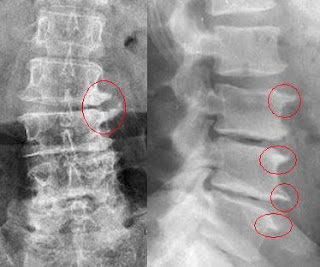

Artrose ou também chamada Osteoartrite, é uma degeneração da cartilagem articular e da porção óssea que é protegida por ela. É também uma enfermidade inflamatória que afeta grande parte das articulações, inclusive a coluna vertebral, com deterioração do próprio disco intervertebral, levando ao longo do tempo deformidades como os osteófitos marginais (Bicos de papagaio).

ARTROSE LOMBAR

A artrose da região lombar se torna mais comum em função da sobrecarga de peso.

DIAGNOSTICO

O diagnostico é feito pelo exame físico, e exames complementares como o RX de coluna.